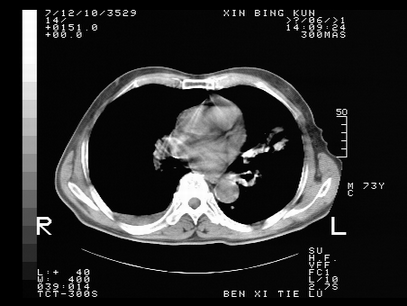

标题: CT10820:男,73岁,病史肺TB,现病史肺炎,直肠CA术后 [打印本页]

标题: CT10820:男,73岁,病史肺TB,现病史肺炎,直肠CA术后

双肺间质改变,依据病史双肺多发结节灶考虑转移,少量胸水.

1.两肺结核.2.两肺多发转移瘤.3右侧少量胸腔积液4.主动脉钙化.

双肺多发结节及条片状致密影,右侧少量胸腔积液。临床:直肠ca术后,肺tb病史。综合考虑:1 双肺转移!2 继发性肺结核合并感染!

此人病史较复杂,原有肺结核,直肠癌术后。肺部病灶形态亦呈多形性。因此,不可仅以一种病来解释肺部的病变。双肺多发的类圆形结节灶,结合病史还是首先考虑转移瘤,而双肺其余病灶还需结合化验室检查,结核或肺部感染在无其它检查资料的情况下不好排除。还是那句话----放射科医生不是开照像馆的,我们也是医生,看片一定要多结合临床及其它检查资料。要当一名合格的放射科医生,并不比当一名临床医生容易,我们可别把自已不当医生看。

两肺多发结节影,并见滋养动脉与其相连,考虑 两肺转移. 右侧胸腔积液考虑胸膜转移.

左肺上叶下叶背段,右肺中下叶见多发斑片状、条索状高密度影,兵变周围小结节影形成“树芽”样改变。 左肺上叶舌段近前胸壁处及右肺中叶内侧段见结节影。右侧胸膜腔内见液体密度区。纵隔内未见明确增大淋巴结。考虑左肺上叶舌段近前胸壁处及右肺中叶转移瘤可能性大。两肺继发型肺结核。右侧胸腔积液。